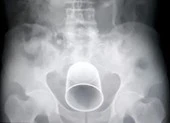

Cái chai sau khi được lấy ra khỏi bụng nạn nhân và hình chụp X-quang trước đó. Ảnh: Shanghaiist

Hình ảnh chụp X-quang cho thấy cái chai đang nằm bên trong cơ thể người đàn ông với phần đầu vươn gần tới ruột. Bác sĩ Lin, người điều trị cho bệnh nhân, nói với các phóng viên rằng ông có thể cảm thấy cái chai khi chạm vào bụng người đàn ông.